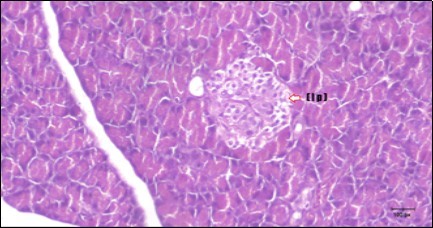

Histological examination of pancreas of the control rats showed normal sized islets of pancreas (Ip) compared to the diabetic rats which showed markedly atrophic islets of pancreas (I.p.) (Figure 8 and Figure 9). Pancreas of in groups (3) and (4) rats showed mild atrophic islets of pancreas (I.p.) with inflammatory cellular infiltrate (Figure 10 and Figure 11). The pancreas of rats in group (5) showed nearly normal islets of pancreas (I.p.) with few inflammatory cellular infiltrate (I.c.) (Figure 12).

Figure 11.Photomicrogragh of pancreas section of treated rat with Glimepiride showing mildly improved of isled of Langerhans with large number of cells (dashed-arrow). (H&E) (40X).

Photomicrogragh of pancreas section of treated rat with Glimepiride showing mildly improved of isled of Langerhans with large number of cells (dashed-arrow). (H&E) (40X).

Histopathological observation in diabetic control showed degenerative changes in both endocrine and exocrine pancreases. A probable explanation may be related to oxidative stress resulting from hyperglycemia which decreases the antioxidants levels and increases ROS 33 and the activities of antioxidant enzyme were altered in diabetic rats. These effects further exacerbate the development and progression of diabetes complications and these may represent the causes of degeneration revealed in histological sections. Fenugreek improved blood glucose levels and insulin, lowered pancreatic islet and β-cells damage which may be attributed to its immune modulatory activity and insulin stimulation action along with its antioxidant potential 32. Glimepiride caused restoration of morphology of beta cell of diabetic and it increased percentage of beta cells 34. This protective effect could be attributed to the antioxidant properties of Glimepiride. Combination therapy improves the protective effect of both therapies alone.